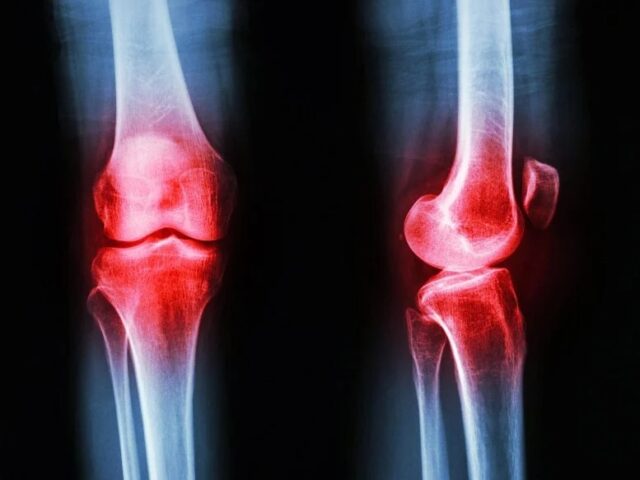

Actualmente se entiende la artrosis como una enfermedad que afecta a toda la articulación, incluyendo el líquido sinovial, los huesos, los ligamentos y los músculos. El ejercicio terapéutico aborda todos estos elementos, especialmente la debilidad muscular, que es uno de los primeros signos de la enfermedad. Programas especializados que se enfocan en la calidad del movimiento y la fuerza han demostrado mejoras significativas en el dolor y la función articular que perduran por meses, ayudando además a reconstruir la confianza del paciente en su propio cuerpo.